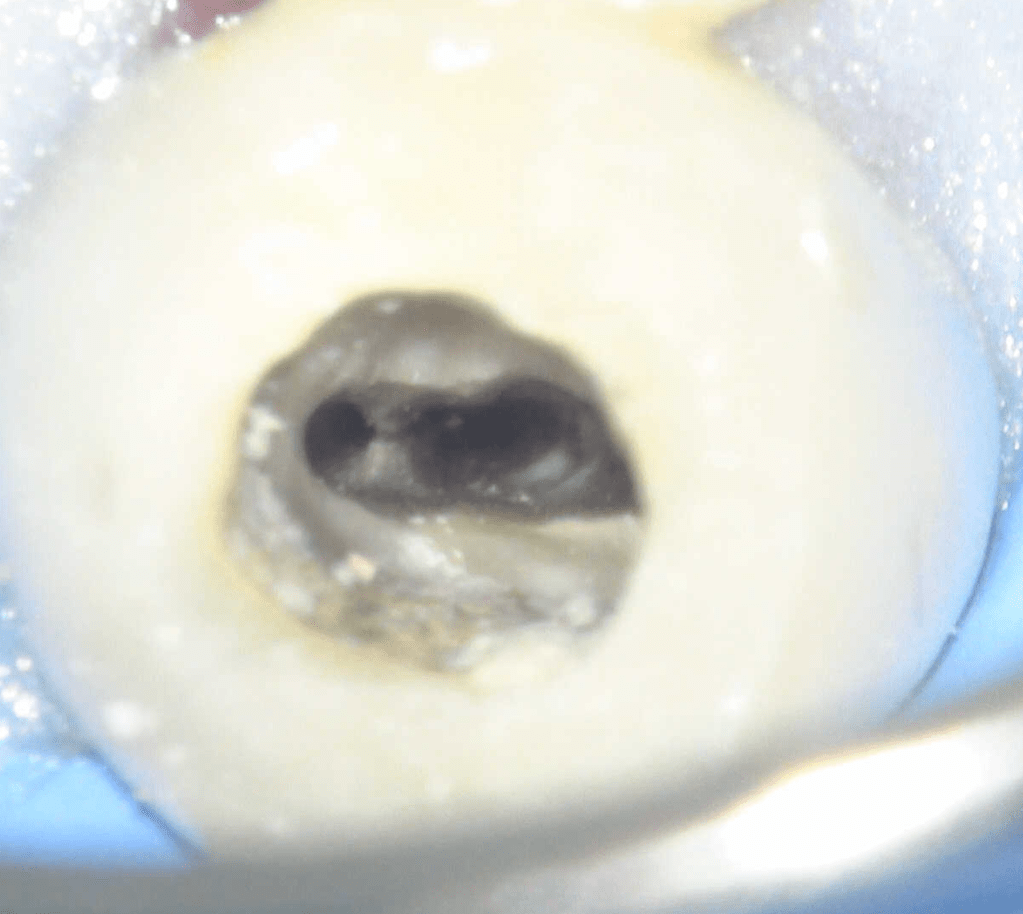

Molar superior

Reco palatina

Reco pared vesticular

Reco pre-endo gingivectomái, pared yuxtaosea

Reco pre-endo, molar inferior

Reco preendo + 4 conductos molar superior

Reco preendo + gingivectomía

Reco preendo, 2o Molar superior

Reconstrucción debajo de puente